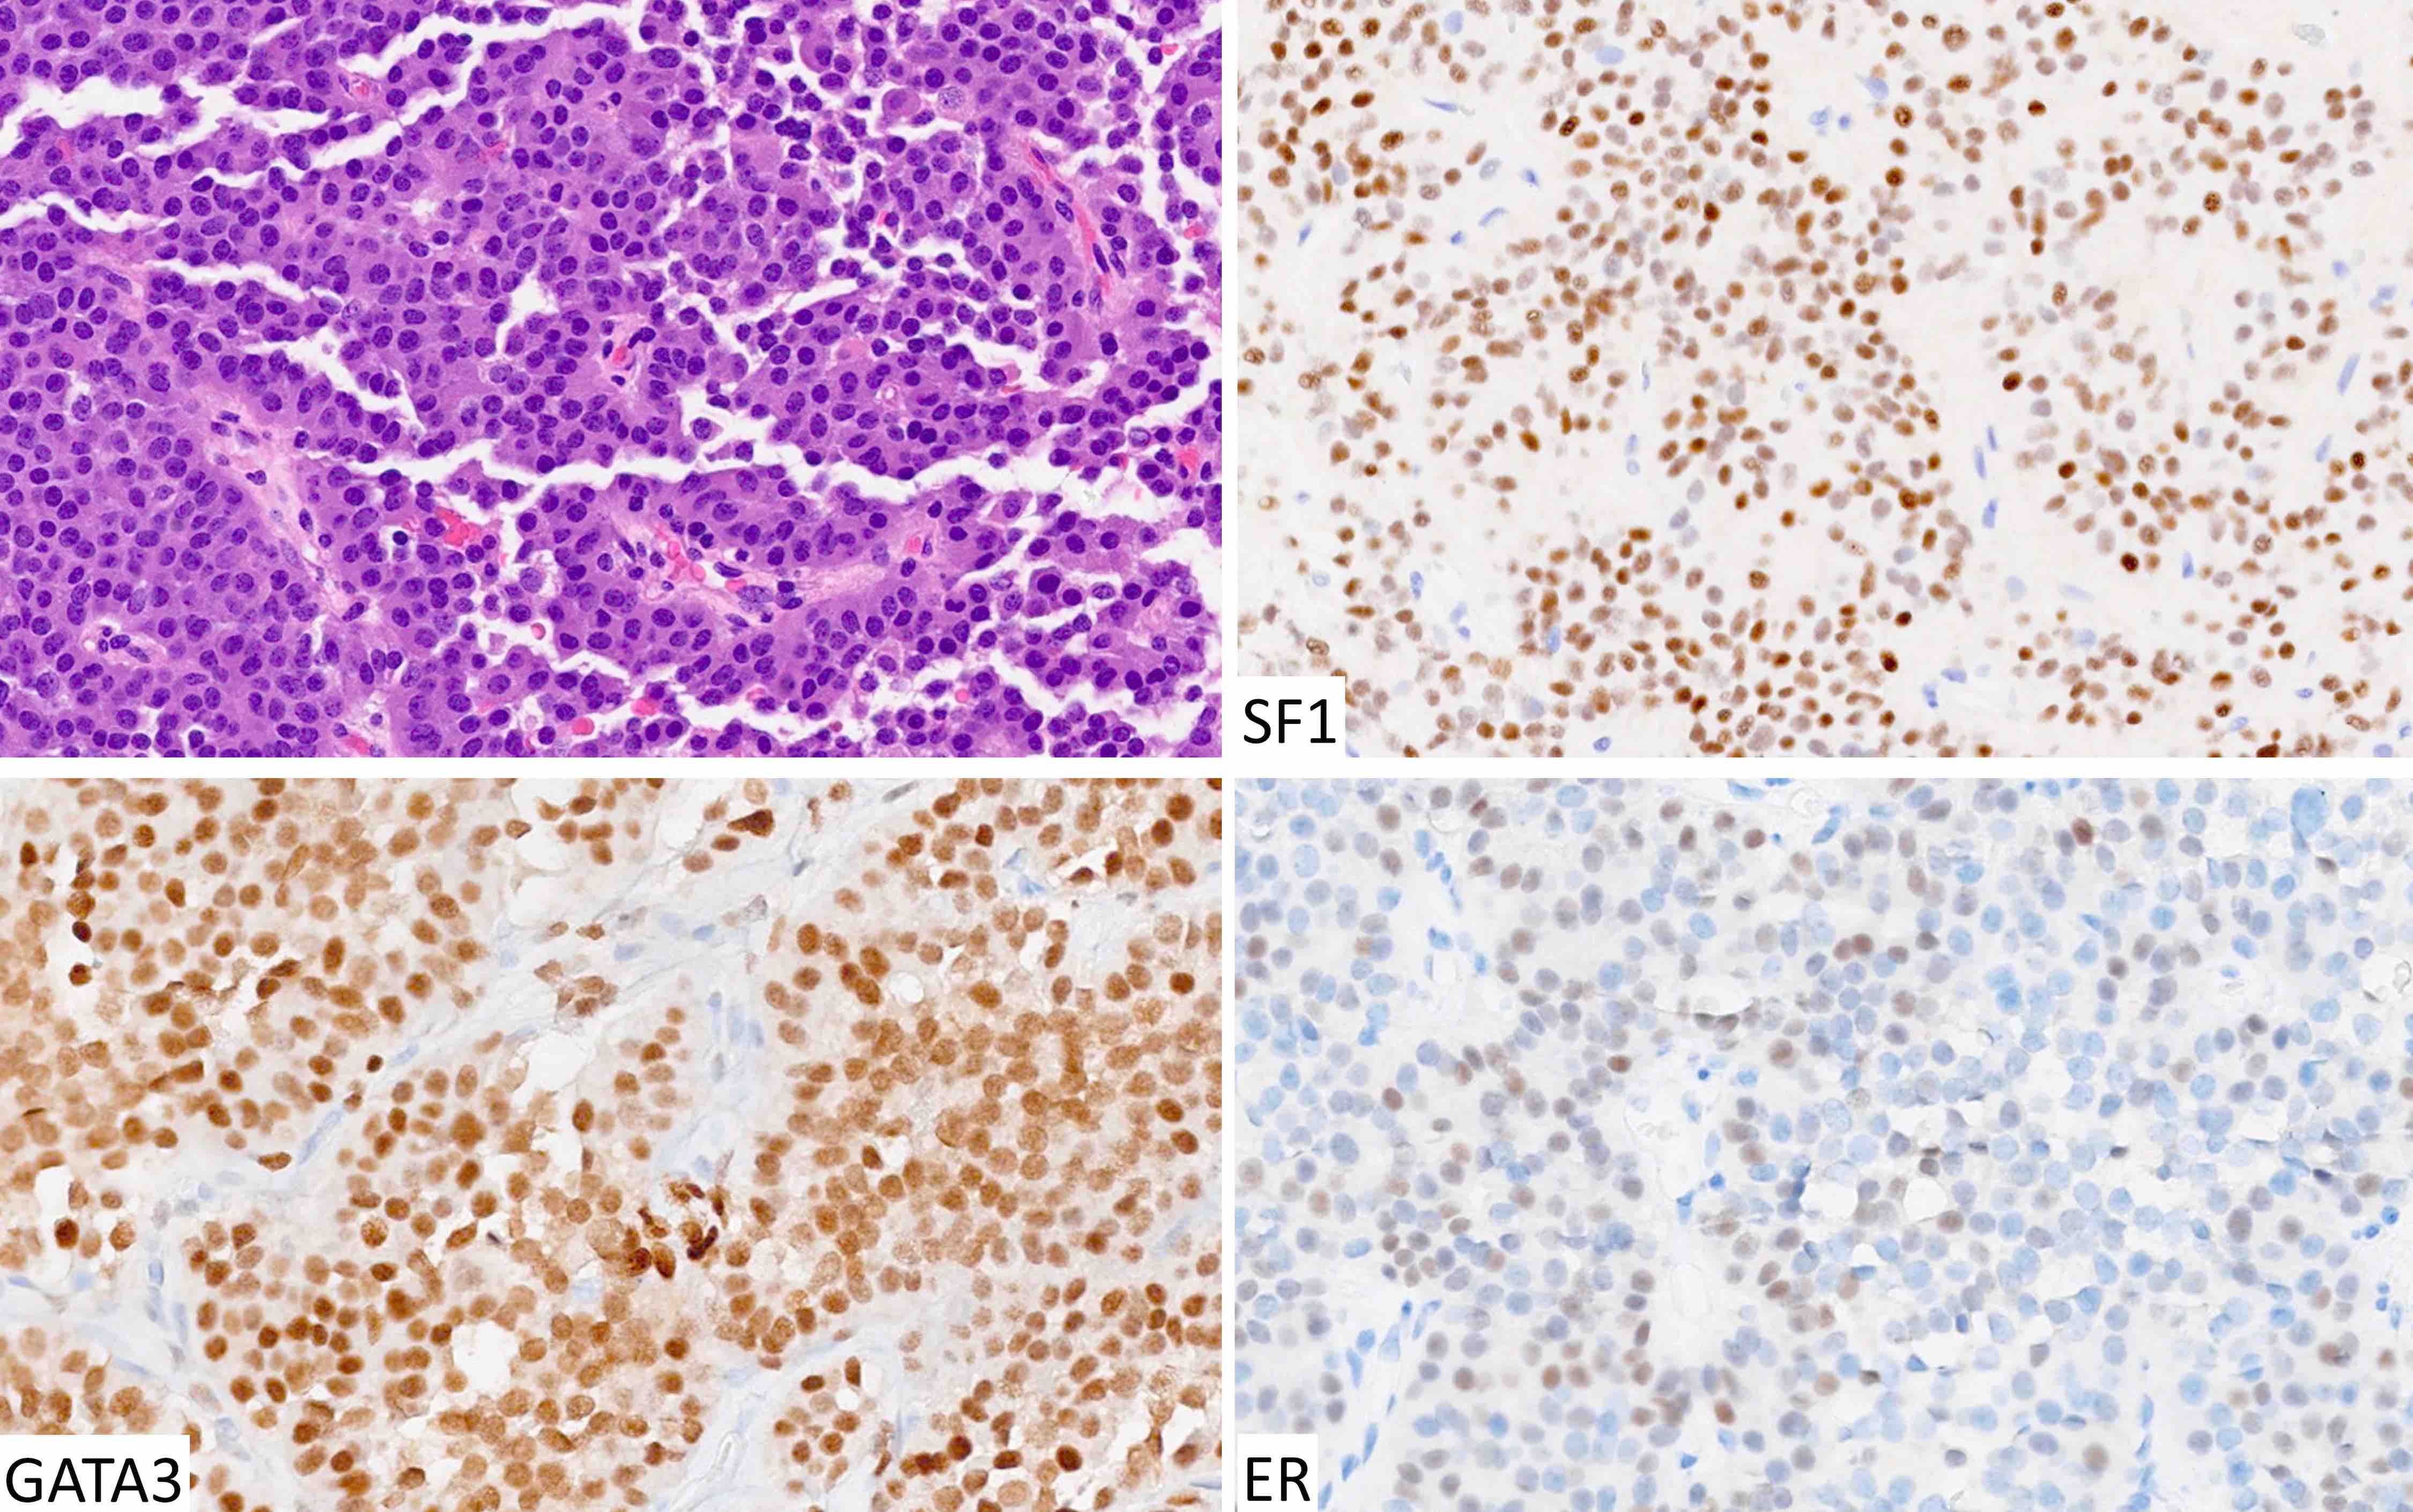

Microscopic (histologic) images

Contributed by Sylvia L. Asa, M.D., Ph.D.

The chromophobic tumor in the image above has the keratin pattern shown on the right. Which of the following is correct?

- This patient had acromegaly

- This patient had Cushing disease

- This patient would not have had hyperprolactinemia

- This tumor is likely to respond to first generation somatostatin analogues

- This tumor stains for Tpit

Practice answer #2

A. This patient had acromegaly. This sparsely granulated somatotroph tumor stains for Pit1 (not Tpit) and causes acromegaly, which may be associated with hyperprolactinemia due to the stalk section effect since sparsely granulated tumors are often large at the time of diagnosis. These tumors generally do not respond to first generation somatostatin analogues. Somatotroph tumors do not cause Cushing disease.